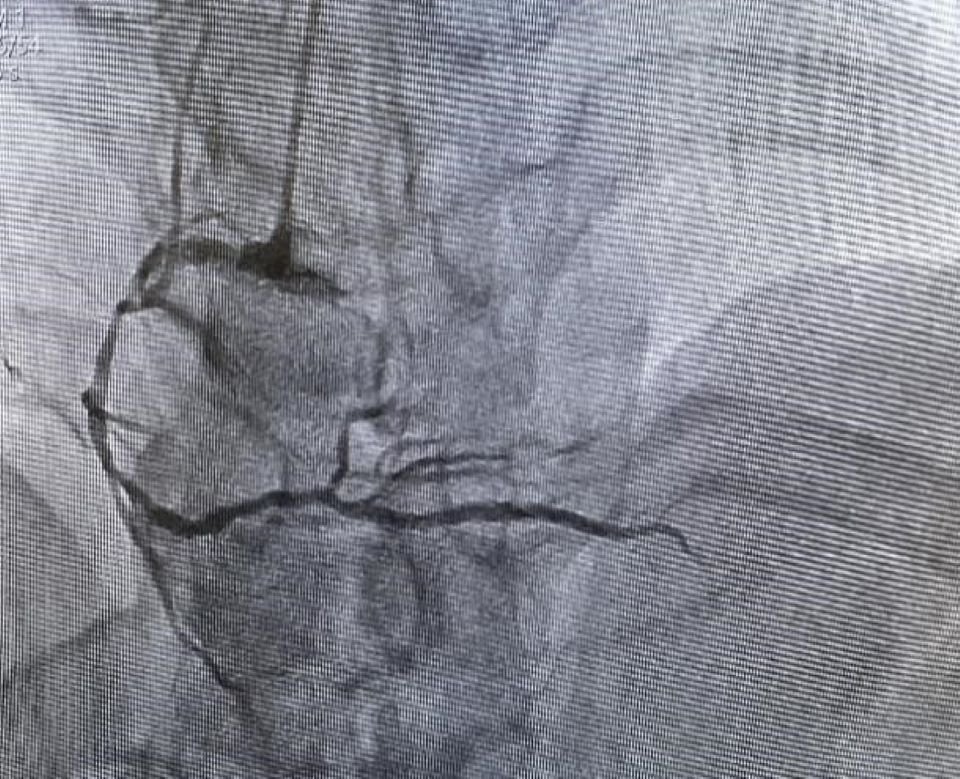

During the procedure, coronary angiography revealed severe lesions in all three coronary arteries. After discussion with local doctors, the CMT decided to treat the right coronary artery. From the selection of medical supplies and coronary puncture to the stent implantation, the CMT carefully explained key points and safety considerations. They guided the local doctors in successfully placing two stents in the right coronary artery, effectively relieving the blockage. The surgery was a complete success.